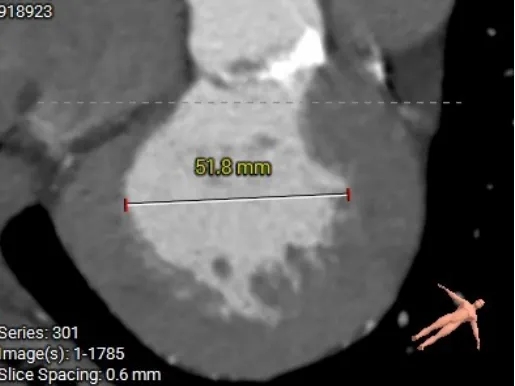

术前CT分析

主动脉根部测量

Annulus 20.7mm

LVOT 21.3mm

钙化积分 612

SOV

27.9*26.8*27.1mm

STJ 22.6mm

AAO 28.8mm

-

三叶瓣

流出道直筒型

重度钙化

STJ及升主无明显扩张